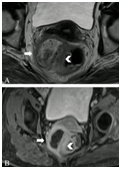

前腹膜返折(APR)是区分腹膜内和腹膜外直肠的重要标志,直肠癌伴腹膜返折受累为T4,增加肿瘤侵入腹腔风险。轴位T2加权像膜返折为薄层中线包绕筋膜返折,称为V型或海鸥征,女性子宫宫颈角和男性精囊腺尖端也是可靠标志(图7)。

图7  腹膜返折。A. 轴位T2加权像海鸥征(长箭头);B. 矢状位T2加权像腹膜返折的线状低密度信号位于子宫宫颈角(长箭头)。

MRI不能显示所有APR,如<1mm低密度线影,此外大的外生性直肠癌、盆腔腹膜脂肪缺乏和术后时APR均较难检测到,如下策略有助于发现APR:获取真正的中线矢状和矢状旁图像;解痉药减少运动伪象改善图像质量;半空膀胱使子宫和前腹壁距离更近,更易鉴别APR;盆底积液也增加发现APR机会。